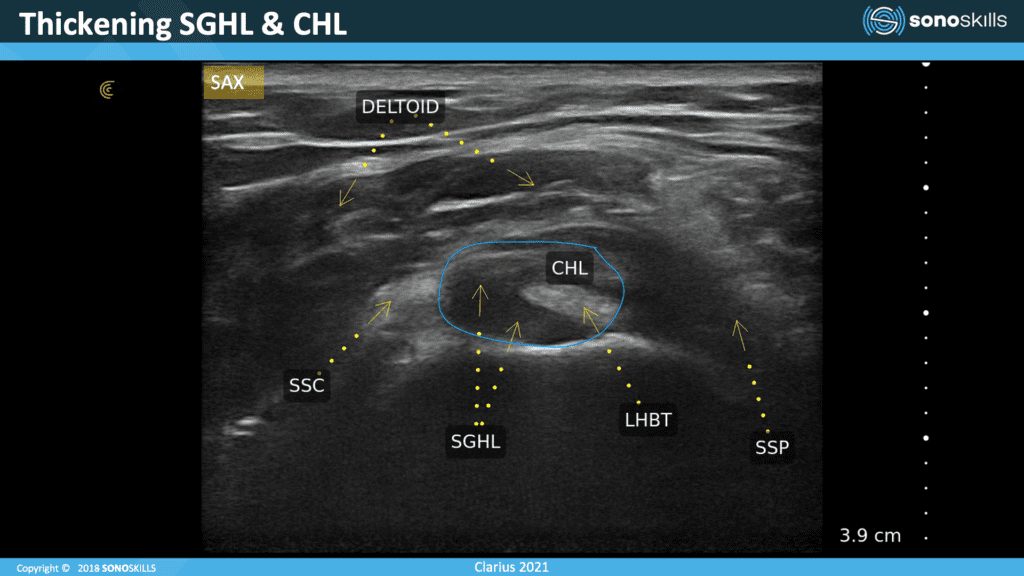

In this image, you see the long head of the biceps, and we can see that the bicep actually looks okay. The bicep doesn’t seem to be tendinopathic, it’s not enlarged. There are no really dark zones, hypoechoic zones within the tendon.

You can see the problem on this side. This superior glenohumeral ligament looks enlarged meaning that the capsule is irritated. At this point, I would switch on Doppler l to see whether there is inflammation here – to see if we can find neovascularization.

The coracohumeral ligaments also looks a little bit thickened. It’s hard to quantify the dimensions of the superior humeral ligament. Use also the other shoulder to compare in the left, right comparisons.

Here we can see a bursa effusion in the superchromial subdelta bursa. In the video we saw that it was only a hypoechoic thin line, but here we can see this effusion. So, we see thickening of the ligaments and also a swelling of the bursa.

This image shows you the increase of the coracohumeral ligament. Sometimes the superior of the coracohumeral ligament can thicken significantly. This is a sign of capsulitis or frozen shoulders.